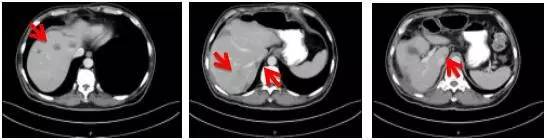

消融后继续原方案治疗6周期,随后以靶向药物贝伐珠单抗维持治疗10个周期。 2016年12月检查发现,患者体内肿瘤进展,需要调整治疗方案。经基因检测,发现KRAS、NRAS及BRAF基因V600E均未突变。遂予化疗伊立替康和靶向治疗药物爱必妥联合治疗,4周期后进入维持治疗。目前,病人一般情况好,肿瘤控制理想。

出现病情进展后给予患者更换靶向治疗药物后,患者治疗效果好,腹腔转移明显好转

2016.11.10

2017.3.13